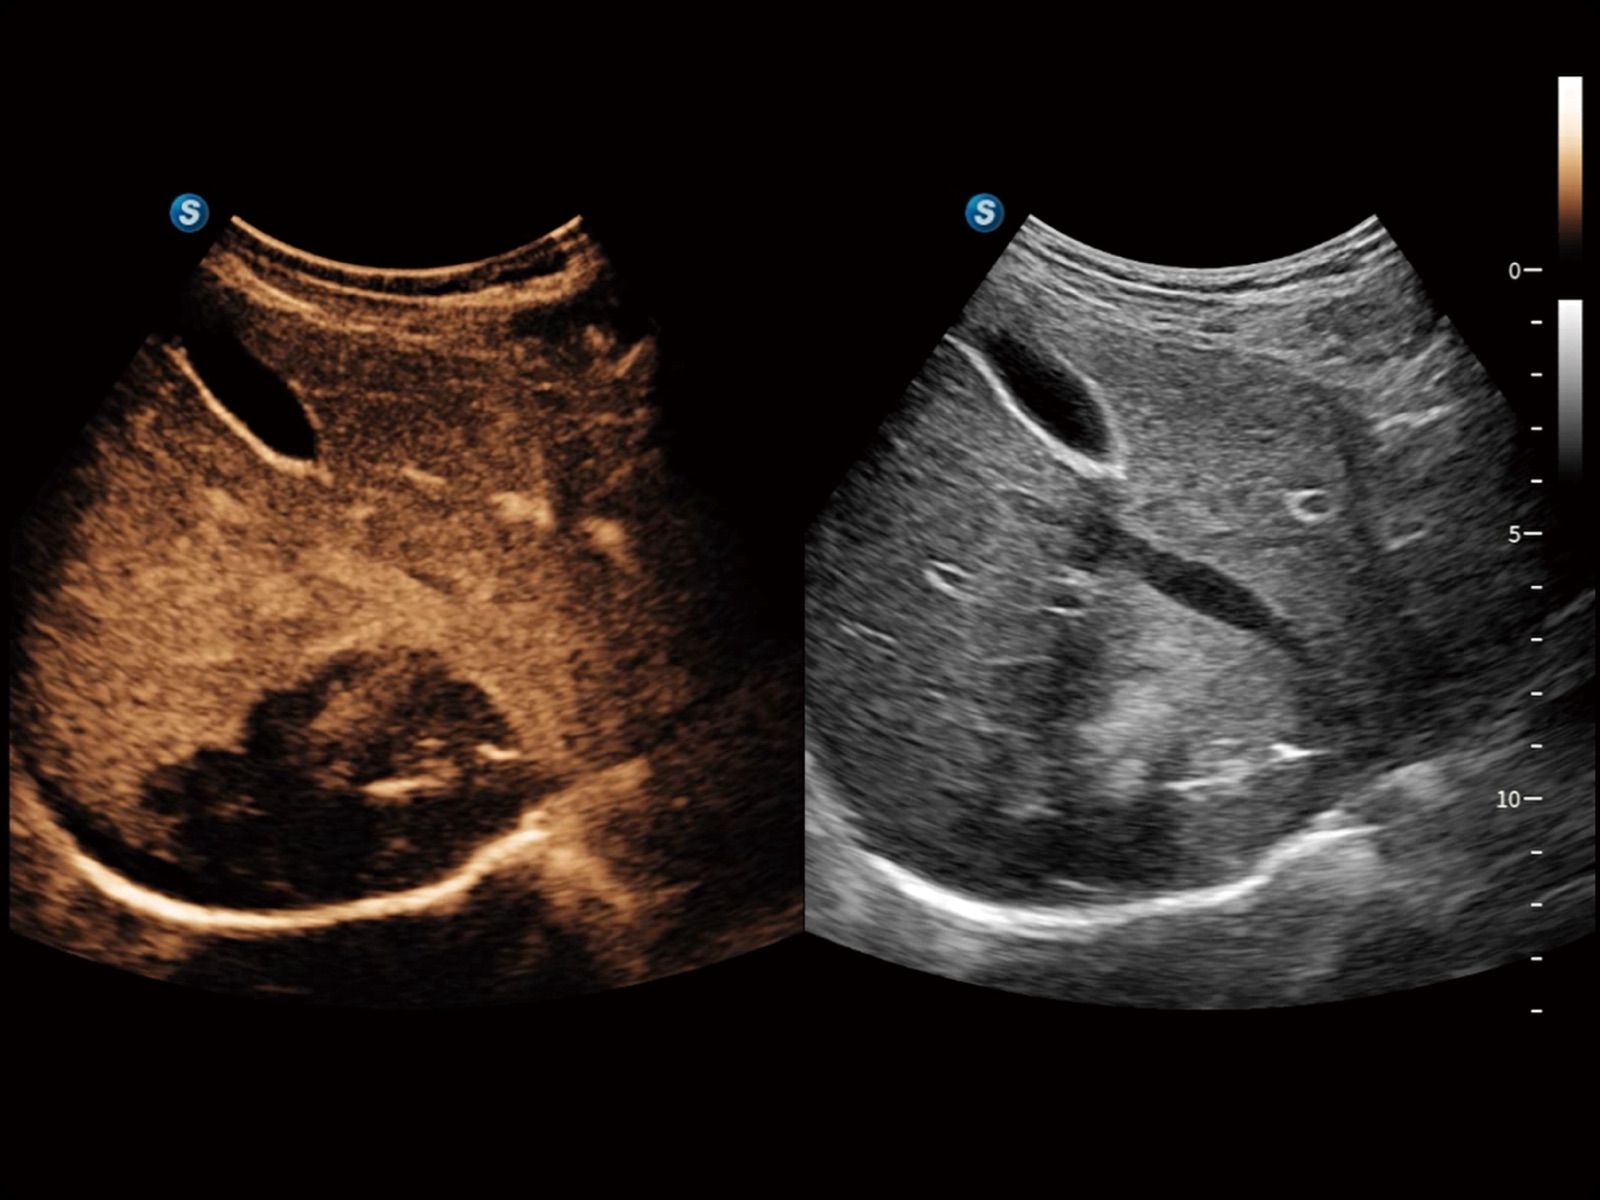

Bright Flow立体血流成像

通过光照模型,使二维血流显示出立体的效果,增加血流的敏感性、成束性,减少外溢。可以和其他不同的血流技术联合使用,轻松应对微小血管,增强血流的立体效果,提升视觉敏感性。